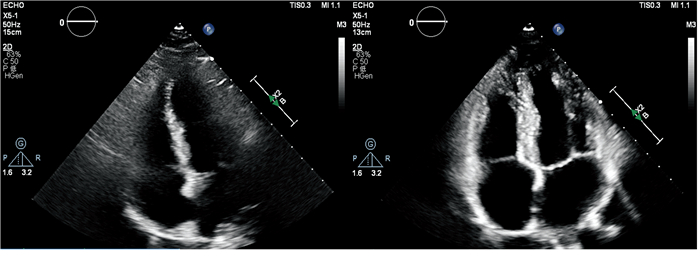

PDCA循环管理法实施后,6个TTE标准切面的质量评分均较实施前提高,其中胸骨旁左心室长轴切面、胸骨旁肺动脉长轴切面、胸骨旁乳头肌水平短轴切面和心尖四腔心切面(图 3)在PDCA循环管理法实施前后的图像质量评分差异有统计学意义(均P<0.05)。见表 2

图  3  PDCA循环管理法实施前后TTE心尖四腔心切面图像质量比较

Fig.  3  Comparison of image quality of apical 4-chamber section in TTE before and after implementation of PDCA cycle management

A: Prior to implementing the PDCA cycle management, the apical 4-chamber section image was blurry with low gain. The lateral wall of the left ventricle, the free wall of the right ventricle, and the left atrial wall were poorly visualized, and the mitral and tricuspid valves were inadequately displayed. B: Following the implementation of the PDCA cycle management, the apical 4-chamber section image was clear with appropriate gain. All cardiac chamber walls, as well as the mitral and tricuspid valves, were distinctly visualized. PDCA: Plan, do, check, act; TTE: Transthoracic echocardiography.